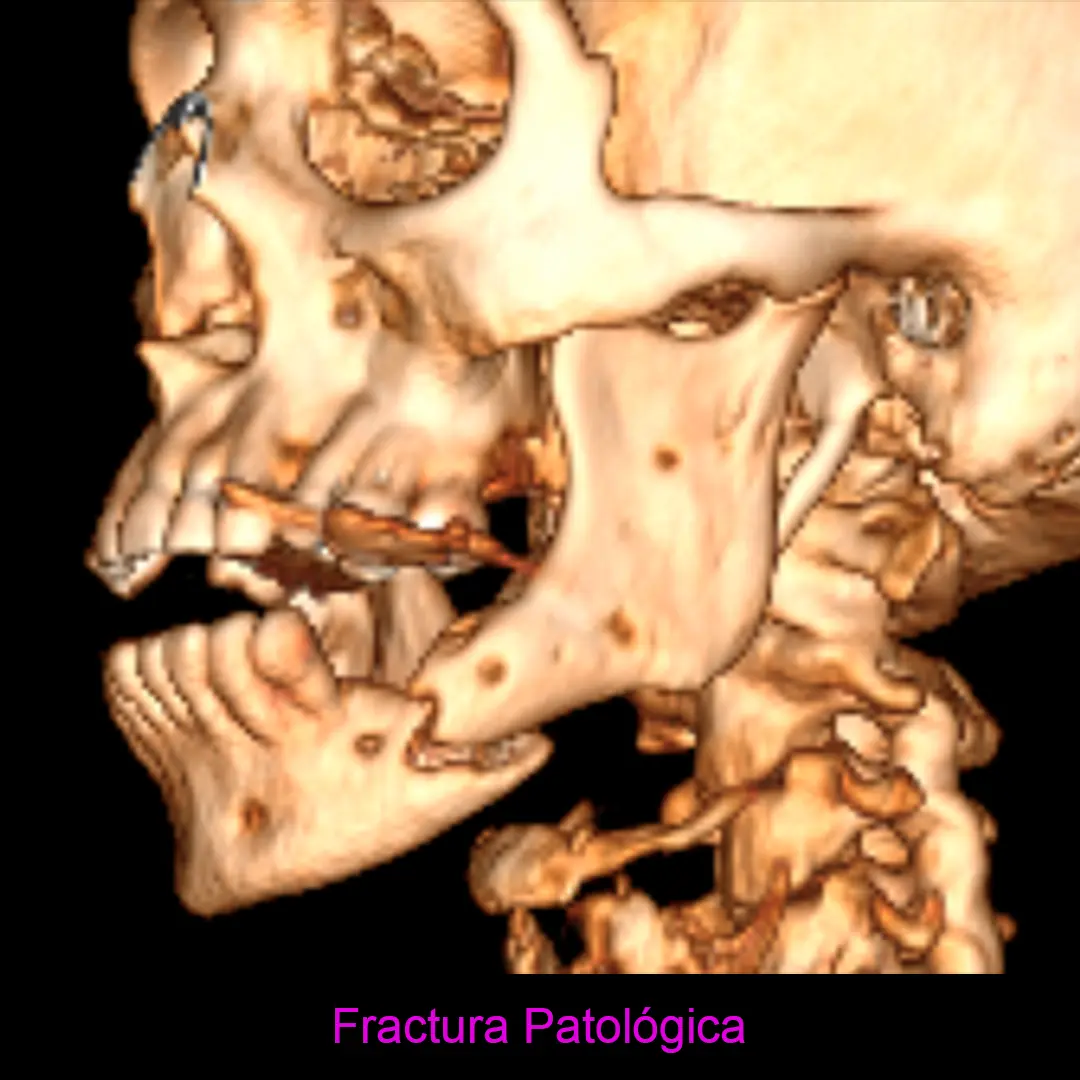

Osteomielitis y osteonecrosis de los maxilares

Entre 2003 y 2004 aparecen en la literatura científica los primeros casos que evidenciaban una asociación entre la administración de bisfosfonatos y exposiciones óseas de evolución tórpida en los huesos maxilares.

Esta enfermedad derivada del tratamiento con ciertos medicamentos que tienen una función esencial en el tratamiento de otras patologías, y suele cursar en el paciente con:

- Dolor

- Supuración (infección)

- Hueso expuesto (que pueden llegar a progresar a fractura patológica)

Se considera un proceso multifactorial, importante papel de la infección, inflamación, sepsis oral y trauma. Patologia qué requiere tratamiento de especialistas altamente calificados.